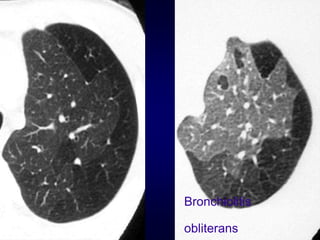

Bronchiolitis obliterans (constrictive bronchiolitis)

Bronchiolitis

obliterans